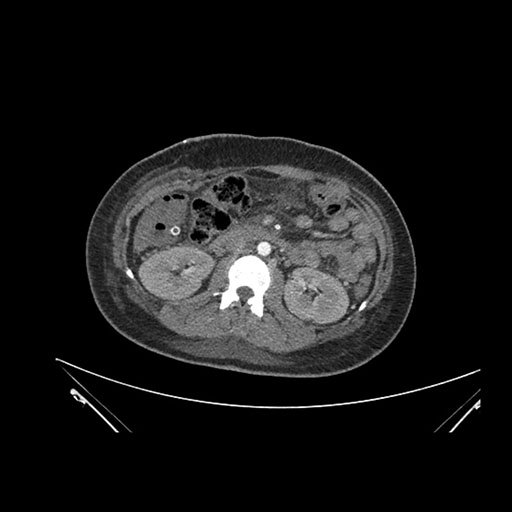

Axial Arterial

Imaging analysis

Based on initial findings, which issue(s) would you be most concerned about?